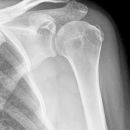

Dislozierte subcapitale Fraktur mit Tbc majus